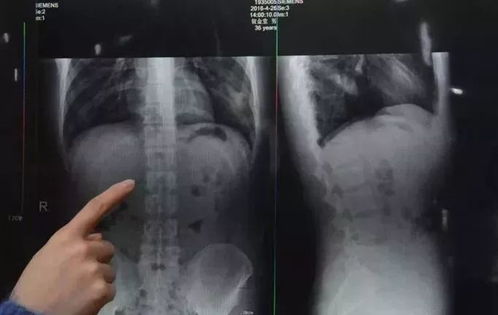

医学上,它是一种罕见的异食癖行为引起的胃石症,患者会反复吞咽自己的毛发,最终在胃内形成一团巨大的毛发结石,有时甚至会延伸到肠道。

早在2022年3月,江苏就有一名9岁女孩因反复腹痛就诊,医生在其胃中取出重达1斤多的毛发结石;同年,陕西一名8岁女孩也因类似症状被确诊。

到了2024年,广东东莞的一位知名小儿外科专家伍岗泉医生,为一名5岁女孩成功进行了胃镜手术,取出了胃里的毛发结石。他表示,这已经不是他第一次遇到这种情况。